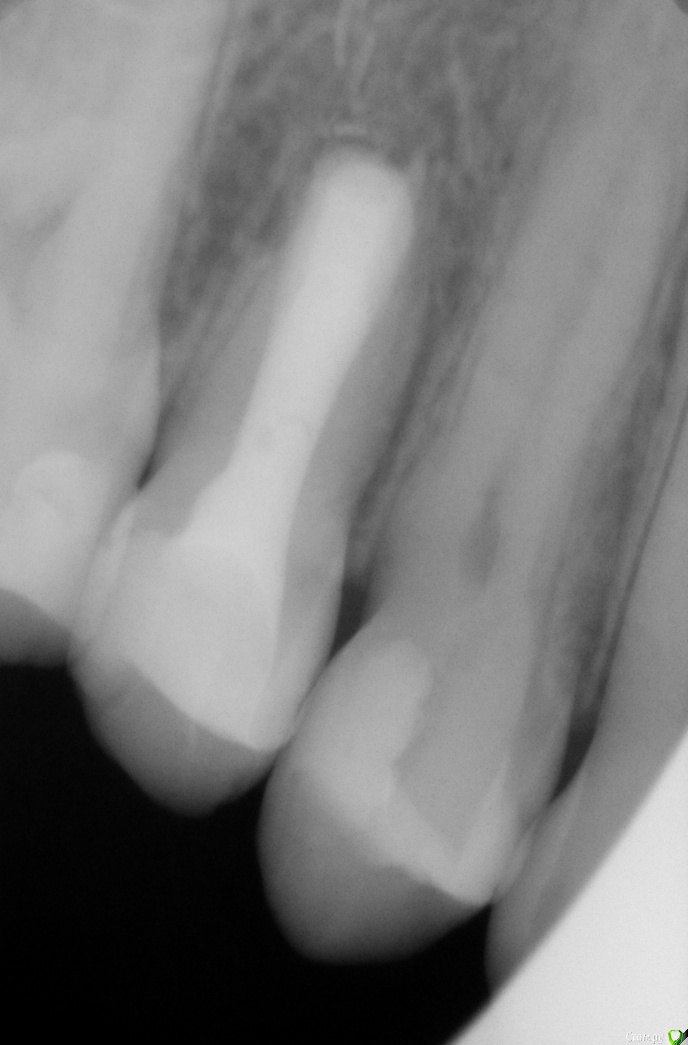

Гарриевич Опубликовано 2 августа, 2018 Автор Поделиться Опубликовано 2 августа, 2018 Вот вся история в картинках 13 Ссылка на комментарий

ger_berra Опубликовано 9 августа, 2018 Поделиться Опубликовано 9 августа, 2018 Вот вся история в картинкахF3CD8F8E-36A2-482B-BFD4-6A0883546283.jpeg2A06B29D-2BDF-4869-A8F8-E02567619146.jpeg47F31C36-F9FE-40C6-9236-3A6203A894B7.jpeg8459AB75-F819-4664-9906-DB4BDCE505D2.jpeg9937DA00-9922-402C-AA29-5DD806AA0714.jpeg37DDB315-6893-49F4-A949-06BC6B58F996.jpegОтличный результат! 1 Ссылка на комментарий